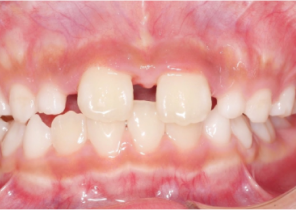

Report sul Caso 1

10 anni 0 mesi, 18 fasi di Invisalign Palatal Expander

Per gentile concessione della Dott.ssa Sandra Khong Tai

Pre espansione Invisalign Palatal Expander

Post espansione Invisalign Palatal Expander

Dopo il trattamento Invisalign First